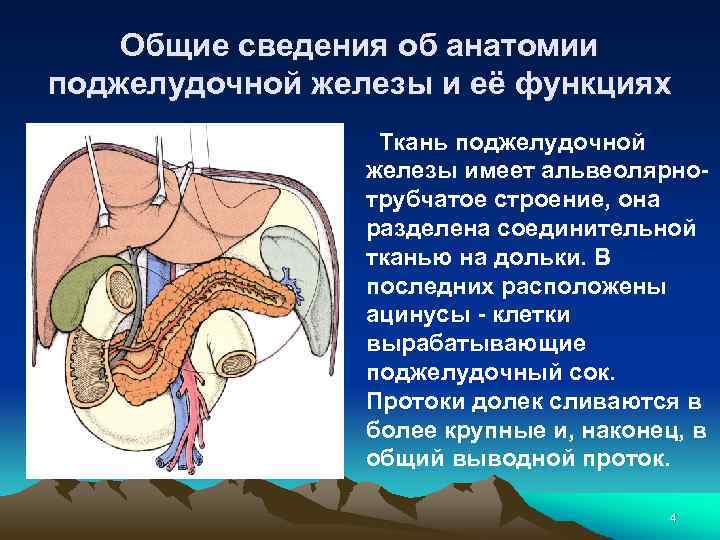

Общие сведения об анатомии поджелудочной железы и её функциях Ткань поджелудочной железы имеет альвеолярнотрубчатое строение, она разделена соединительной тканью на дольки. В последних расположены ацинусы - клетки вырабатывающие поджелудочный сок. Протоки долек сливаются в более крупные и, наконец, в общий выводной проток. 4

Общие сведения об анатомии поджелудочной железы и её функциях Эндокринная часть расположена в виде небольших скоплений инсулоцитов, не имеющих протоков в толще долек. (Островки Лангерганса). Клетки островков Лангерганса вырабатывают инсулин, глюкагон и другие гормоны, непосредственно поступающие в кровь. В поджелудочном соке (его выделяется до 2 литров в сутки) содержится 3 группы ферментов - амилазы - переваривающие углеводы, протеазы - расщепляющие белки и липазы - разрушающие жиры. 5